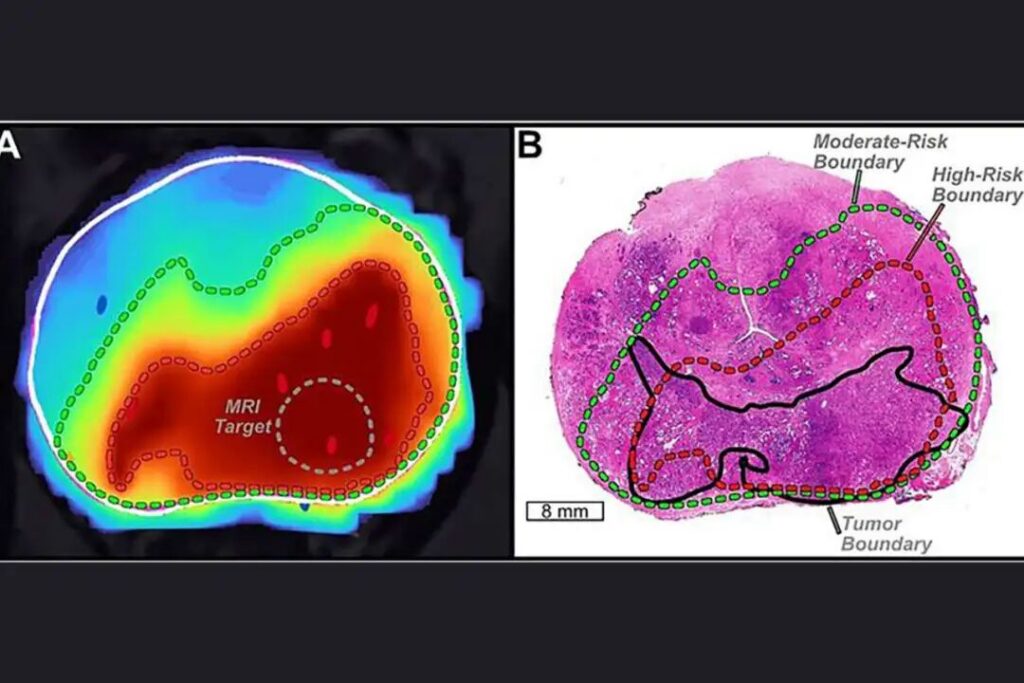

前列腺癌:Unfold AI

为提升前列腺癌的诊断与治疗精度,UCLA 研究人员开发了 Unfold AI。

这项技术可将传统 MRI 影像升级为高度精细的”肿瘤地图”,为医生提供更清晰的决策依据。

在一项研究中,面对极易被忽视的”精囊受累”情况,传统 MRI 的检出率仅为 52%,而 Unfold AI 的检出率高达 92%。

有了这张”高清导航图”,医生得以避开盲区,直达病灶。